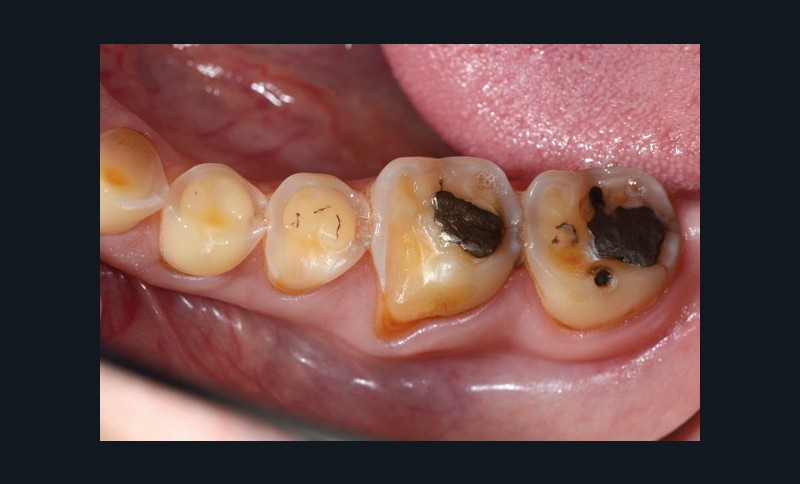

À l’examen clinique (fig. 2 à 4), on observe :

– l’absence de 17, 27 et 47 (suite de lésions carieuses volumineuses) ;

– un parodonte sain ;

– des érosions sévères généralisées, symétriques et bilatérales (occlusales, palatines et vestibulaires au maxillaire) ;

– des lésions carieuses débutantes de site 3 ;

– des obturations préexistantes infiltrées ;

– une vitalité pulpaire conservée sauf au niveau des prémolaires maxillaires ;

– une usure des bords libres des incisives mandibulaires